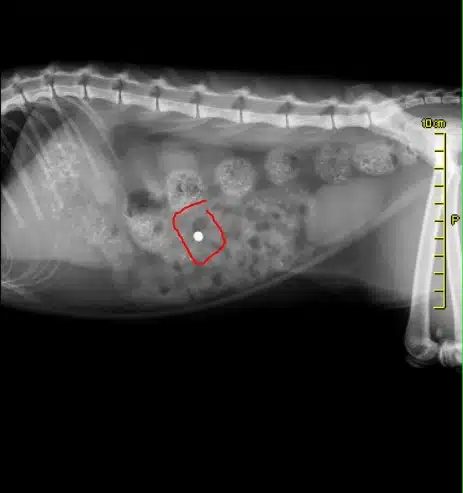

È un caso? Ah, sembra che si diverta a sparare anche agli uccelli, come le tortorelle? forse. Anni fa anche il mio gatto subì lo stesso trattamento: venne colpito sul fianco con un pallino, che scoprii solo successivamente quando lo portai dal veterinario per una radiografia (foto a fondo pagina).

Il veterinario mi disse che aveva un pallino conficcato nel fianco. Perché scrivo tutto ciò? Una denuncia non servirebbe a nulla, per vari motivi (a volte non succede nulla nemmeno quando uccidono delle persone, figuriamoci dei gatti).